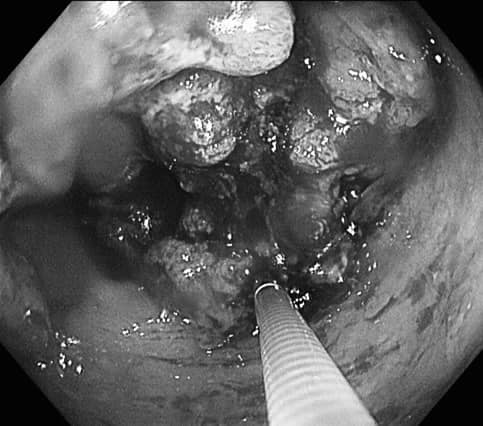

禾馨民權健康管理診所腸胃科醫師詹宜學在臉書粉專《肝膽腸胃科 詹宜學醫師》分享案例時表示,這名患者本身患有糖尿病,因持續腹瀉了半年被女兒發現不對勁帶去就診;由於糖尿病患者不能空腹太久,擔心血糖太低會有危險,所以該患者無法在檢查前3天執行低渣飲食,也不能分2次喝清腸藥,甚至半夜起床清腸,於是詹醫師幫病人安排了「當日清腸,下午檢查」的選項。最後胃鏡檢查結果為胃潰瘍合併幽門桿菌感染、大腸鏡顯示乙狀結腸癌,約7公分長,幾乎造成完全的腸道阻塞。

詹宜學醫師 授權提供 哪些人屬於大腸癌的高危險群?